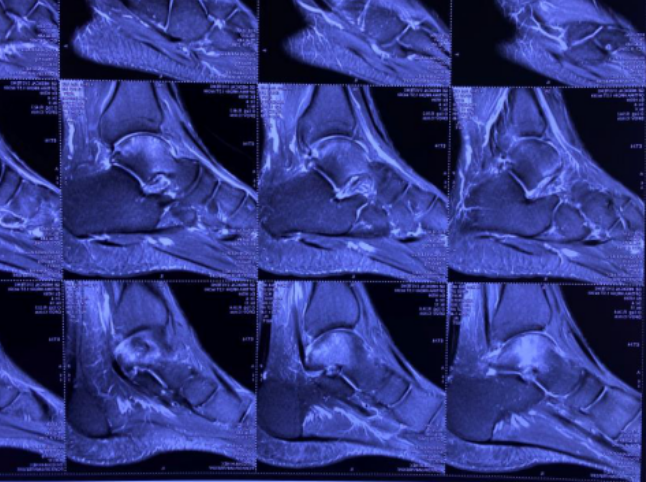

术前磁共振片

29岁的邵先生是铜山大许镇人,9个月前扭伤右脚踝,起初没当回事,后来因为行走疼痛不断加重,3个月后在外院检查出距腓前韧带断裂,做了右距腓前韧带锚钉修复术。术后,小邵行走时踝关节外侧疼痛明显缓解,但踝关节内仍不时有酸痛感。因为酸痛感逐渐加重,半个月前,小邵在他院做磁共振,查出“右距骨剥脱性骨软骨炎”,随后他来到betway在线登陆足踝科治疗。

在sararz,小邵的检查结果显示右距骨上缘关节面下囊变,剥脱性骨软骨炎,足踝科关节镜团队经过讨论,决定给患者进行“踝关节镜下清理距骨微骨折术”。